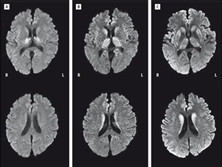

头部MRI、头部CT、脑电图(EEG)、气脑造影

克-雅氏病性痴呆的临床检查手段

克-雅氏病性痴呆应该做哪些检查?